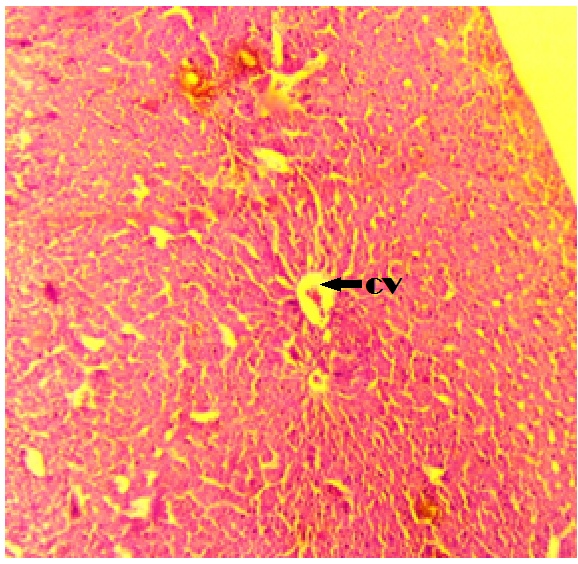

Light microscopic observations in the tissues of Mystus gulio fishes treated with SNP are presented in fig. 2-4. Primary and secondary lamellae of gills with pillar cells and also the presence of chloride cells were evident in control animals. Fishes exposed to green synthesized silver nanoparticles shows necrosis in the gill arch (GA) and fusion of primary and secondary lamellae. Observation reveals hyperplasia and aneurism. The liver was covered with serous membrane and some connective tissues were extended in the parenchyma. In the control tissue presence of polygonal hepatic cells with a clear spherical nucleus was evident. The presence of glycogen granules was also observed and necrosis of hepatocytes was evident in the treated groups. The shape of the cells with irregular vacuolization was also observed in AgNP's treated liver tissue of freshwater fish Mystus gulio. The muscle tissue of control fishes shows the bundle of myofibrils with well-defined striation.

Fig. 3A: Photomicrograph of control liver tissue of freshwater catfish Mystus gulio HC-Hepatic cell, CV-central vein

Fig. 3B: Morphology of liver tissue of silver nanoparticle-treated fresh water cat fish Mystus gulio NHC-necrotic hepatic cells, VC-vacuolization, DN-disintegrated nucleus BS-blood sinusoids